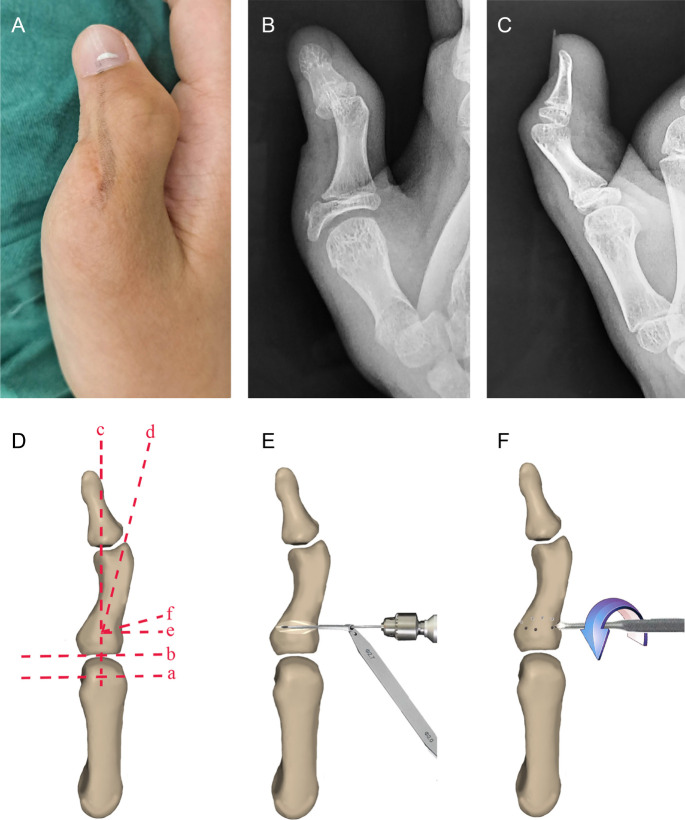

Objective: This study aimed to introduce a minimally invasive technique in correcting residual zigzag deformities after early treatment of thumb duplication followed by fixation with a cemented frame.

Methods: Nineteen patients (14 males, 5 females; mean age, 12 years; age range, 8-14 years) with residual zigzag thumb deformities were treated with the minimally invasive technique from 2017 to 2019. The function and cosmesis of the thumbs were assessed using the Japanese Society for Surgery of the Hand.

Results: The mean period between the first and the second operations was 35 months (range, 12-84 months). There were Wassel types III (n=4), IV (n=13), and V (n=2) residual zigzag thumb deformities. Preoperatively, the mean alignment deformities of the interphalangeal and metacarpophalangeal joints were 23° (12-42°) and 18° (11-33°), respectively. The mean function and cosmesis of the thumbs were 12 points (range, 8-14 points). There were 1 fair and 18 poor scores. At the final follow-up (mean, 28 months; range, 24-33 months), the mean alignment deformities of the interphalangeal and metacarpophalangeal joints were 1° (0-4°) and 18° (0-4°), respectively. The mean function and cosmesis of the thumbs were 18 points (range, 16-20 points). There were 5 excellent results, 13 good results, and 1 fair result.

Conclusion: Residual zigzag thumb deformities can be successfully corrected with the minimally invasive technique, resulting in good functional and cosmetic outcomes. The technique can be used as an alternative in selected cases.